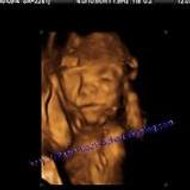

Ma grossesse, mon fils!

Photo 014

Uploaded: October 19, 2006 Views: 147